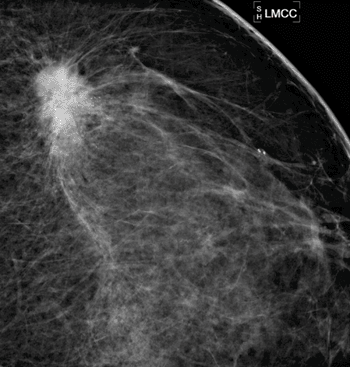

Что показывает маммография и рак груди на маммограмме . Как выглядит рак на маммографии . Чаще всего рак молочной железы на маммограмме выглядит как интенсивная тень - лучистая "звезда" белого цвета - смотрите фото .